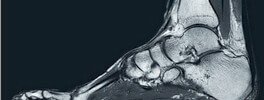

Orthopedic